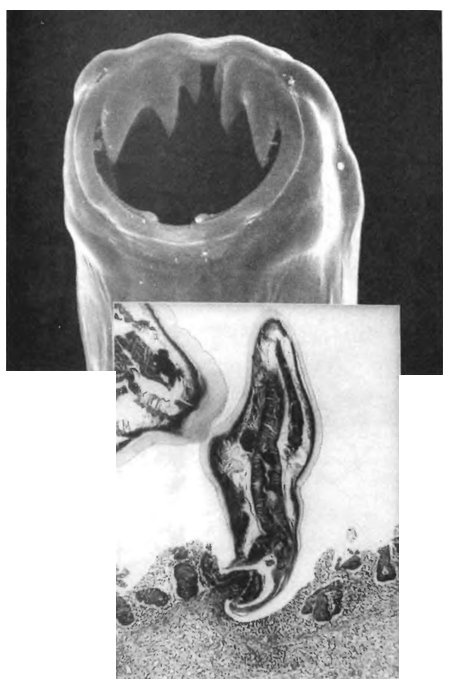

![]() Анкилостому носит в себе 1,3 млрд человек. При помощи своих мощных зубов эти паразиты рассекают стенку кишечника (врезка) и пьют кровь из раны. ![]() Ленточные черви, достигающие в длину более 15 м, являются самыми крупными паразитами человека. ![]() Известно пять тысяч видов ленточных червей, живущих в самых разных животных, и, вероятно, многие тысячи из них еще ждут своего открытия. Головки особей каждого вида специально приспособлены для закрепления в теле хозяина. ![]() Шистосомой (известна как кровяной сосальщик) заражены более 200 млн человек. Слева вверху: молодые паразиты вылупляются из яиц в пресной воде и ищут нового хозяина — улитку. Справа вверху: внутри улитки паразиты проживают несколько поколений, прежде чем превращаются в ракетообразные существа, известные как церкарии. Внизу: церкарии проникают в организм человека сквозь кожу, достигают зрелости и окончательно поселяются в венах хозяина. ![]() Trichinella, вызывающая трихинеллез, является исключительным паразитом: это животное с образом жизни вируса. Ее личинки проникают в отдельные мышечные клетки и, сворачиваясь внутри в клубок, берут под контроль мышечную ДНК, что помогает им сделать клетку более удобным жилищем. ![]() Вверху: одноклеточный паразит Plasmodium falciparum, вызывающий малярию. На фото — новое поколение паразитов выходит из эритроцита. Слева внизу: еще один одноклеточный паразит — Trypanosoma brucei, вызывающий сонную болезнь. Справа внизу: Toxoplasma gondii (показанная здесь внутри клетки хозяина) является одним из наиболее успешных паразитов на Землей в некоторых районах мира ею инфицировано 90 % населения. ![]() Паразиты часто выбирают строго определенные — и весьма странные — места для жизни. Эти ракообразные устраиваются во рту рыбы, съедают ее язык и занимают его место. После этого они начинают выполнять функции языка: рыба может с их помощью хватать и глотать добычу. ![]() Еще один замечательный паразит — Ommatokoita elongata — живет только в гренландских акулах, которые путешествуют под арктическими льдами. Более того, Ommatokoita живет только в их глазах, закрепляясь в стекловидном теле глаза с помощью специально приспособленных ног. ![]() Насекомые — мастера паразитировать на других насекомых. Вверху: паразитические осы откладывают яйца внутрь гусениц, и личинки медленно пожирают своих хозяев живьем, прежде чем выползти наружу и окуклиться. Внизу: насекомое Xertos peckii паразитирует на непаразитической бумажной осе. Когда из яиц выходят личинки, самка остается внутри и поедает половые органы хозяина, а самец пробуривается наружу и летит к другой осе, чтобы найти себе пару. Во взрослом состоянии самец живет всего несколько часов; в результате он развил у себя замечательный орган, помогающий ему быстрее отыскать самку. У самца 100 миниатюрных глаз, каждый из которых имеет собственную радужную оболочку и способен сформировать полное изображение. ![]() Когда паразит полностью использовал своего хозяина, ему необходимо выбраться наружу. Вверху: грибок вырастает из муравья. Внизу: червеобразный паразит, известный как нематоморф, выходит из своего хозяина — сверчка. ![]() Колючеголовые черви, подобно многим другим паразитам, успевают пожить в двух и более хозяевах. Многие из них сначала живут в насекомых и ракообразных, а затем перемещаются в хищников, например в птиц. Чтобы попасть в этих хищников, паразиты делают своих промежуточных хозяев глупыми и беспечными — легкой добычей для хищников. ![]() Вверху: паразитический рачок Sacculina carcini проникает в краба и заполняет все его тело целой сетью «корней». На том месте, где у краба должна находиться специальная сумка для яиц, Sacculina формирует мешочек, полный личинок (среднее фото), и вынуждает краба заботиться не о своем потомстве, а о потомстве паразита. Внизу: улитка тоже может стать жертвой паразита — трематоды Leucochloridium paradoxum. Окончательные хозяева этого паразита — птицы. Чтобы привлечь их внимание, Leucochloridium забирается в прозрачные щупальца улитки. Полосатые трематоды просвечивают сквозь щупальца, напоминая гусениц, и голодные птицы с готовностью хватают зараженных улиток. |